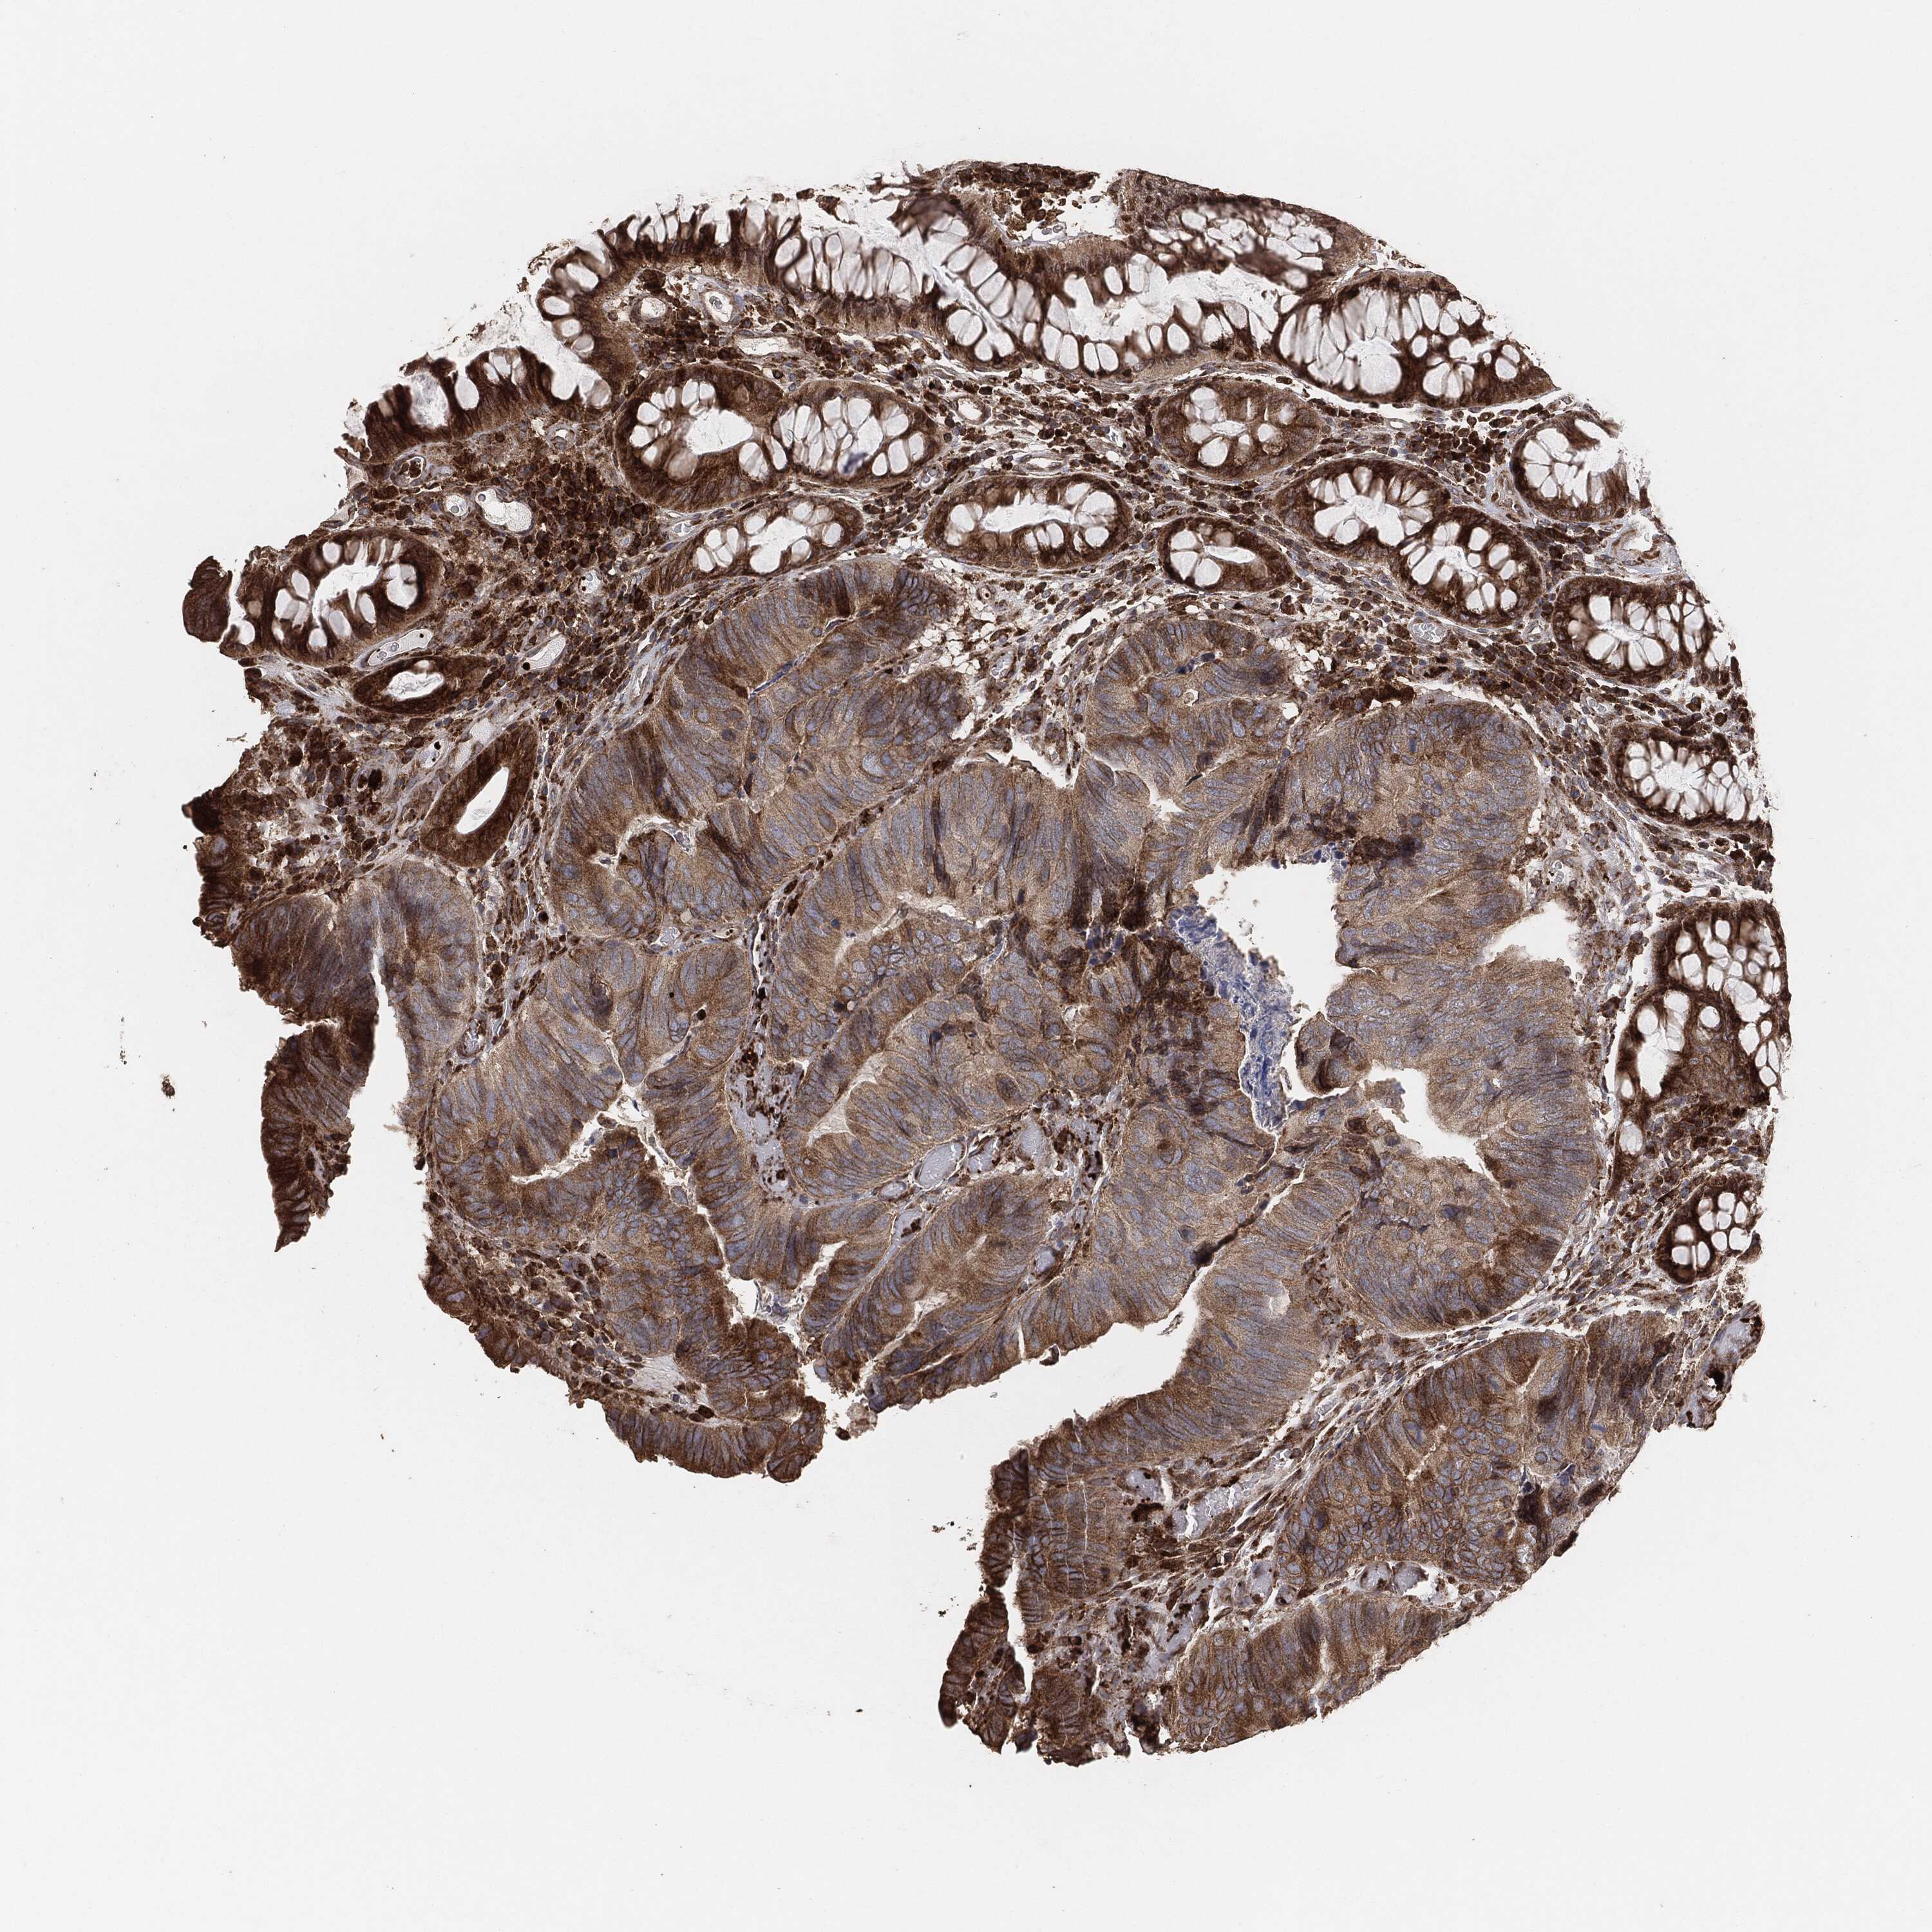

CANCER COLORECTAL CANCER Show tissue menu

Colorectal cancer

Human cancer

Colon adenocarcinoma